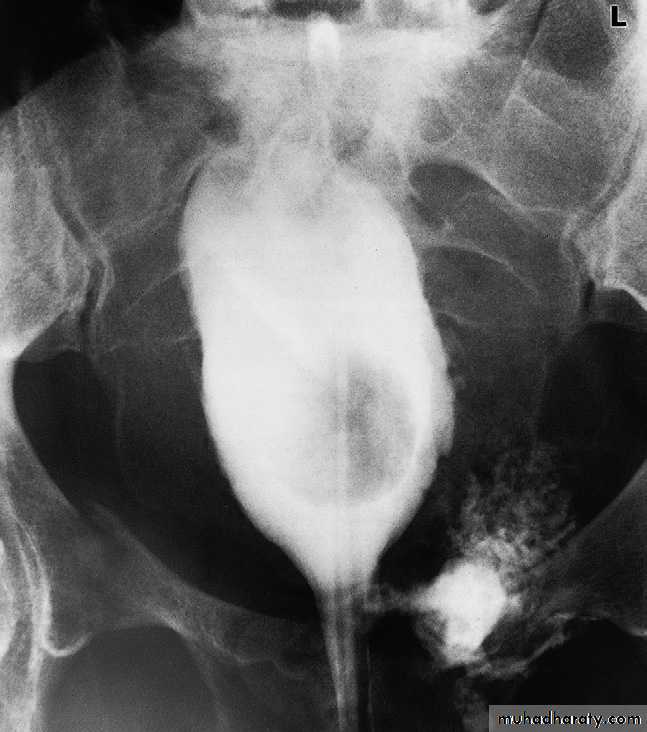

There are two basic types of neurogenic bladder :

1.The large, atonic, smooth-walled bladder with poor or absent contractions and a large residual volume.

2.The hypertrophic type, which can be regarded as neurologically

induced bladder outflow obstruction. In this condition, the bladder is of small volume, has a very thick, grossly trabeculated wall and shows marked sacculation .